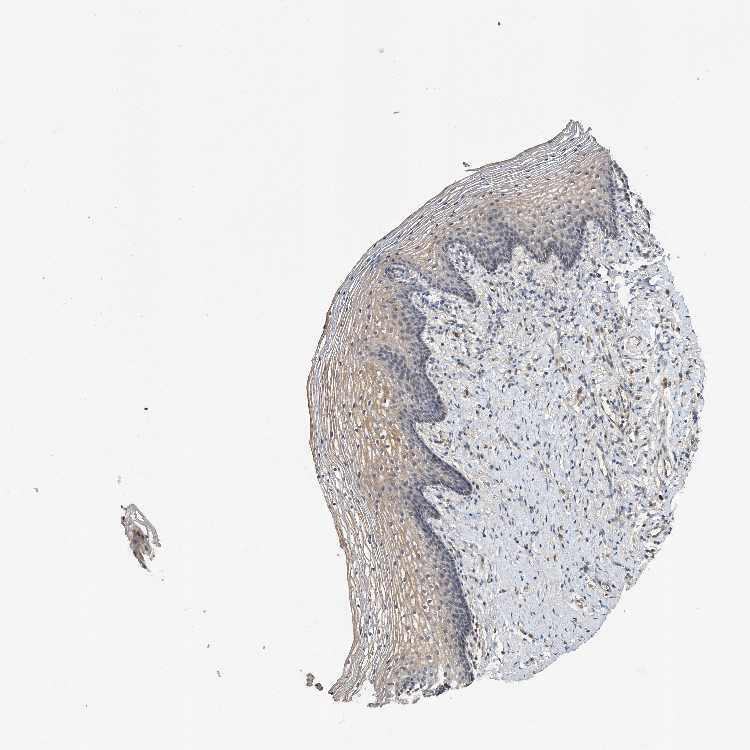

TISSUE PRIMARY DATA VAGINA Show tissue menu

VAGINA - Antibody stainingi

Antibody staining in the annotated cell types in the current human tissue is reported as not detected, low, medium, or high, based on conventional immunohistochemistry profiling in selected tissues. This score is based on the combination of the staining intensity and fraction of stained cells.

Each image is clickable and will lead to virtual microscopy that enables deeper exploration of all samples and also displays staining intensity scores, fraction scores and subcellular localization as well as patient and tissue information for each sample.

Antibody HPA030636Antibody CAB025481

Squamous epithelial cells Not detectedLow